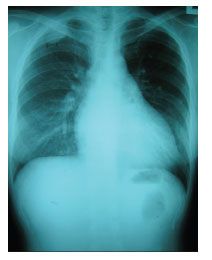

Physical examination revealed right sixth cranial nerve palsy with mild spastic paraparesis. Her CD4+ cell count now was 50/µL, and her plasma HIV RNA level was below 50 copies/mL. A chest radiograph showed an extrapleural mass at the apical area of the right lung (Figure 1). A CT scan of the brain showed an enhancing extradural mass about 4 cm in diameter at the medial part of the right tentorium cerebelli, with erosion of the petrous apex and extension into the right optic canal and prepontine cisterns, encasing the right carotid (cavernous portion) artery (Figure 2). In addition, another extradural mass at the left cavernous sinus extending into the left optic canal and orbital apex was noted. A T1-weighted MRI scan of the spinal cord showed 2 enhancing extradural hypointense lesions about 3 cm and 1 cm in diameter at the right neural foramina of L3 and S1, respectively (Figure 3).

Figure 1.A chest radiograph showed an extrapleural mass at the apical area of right lung.